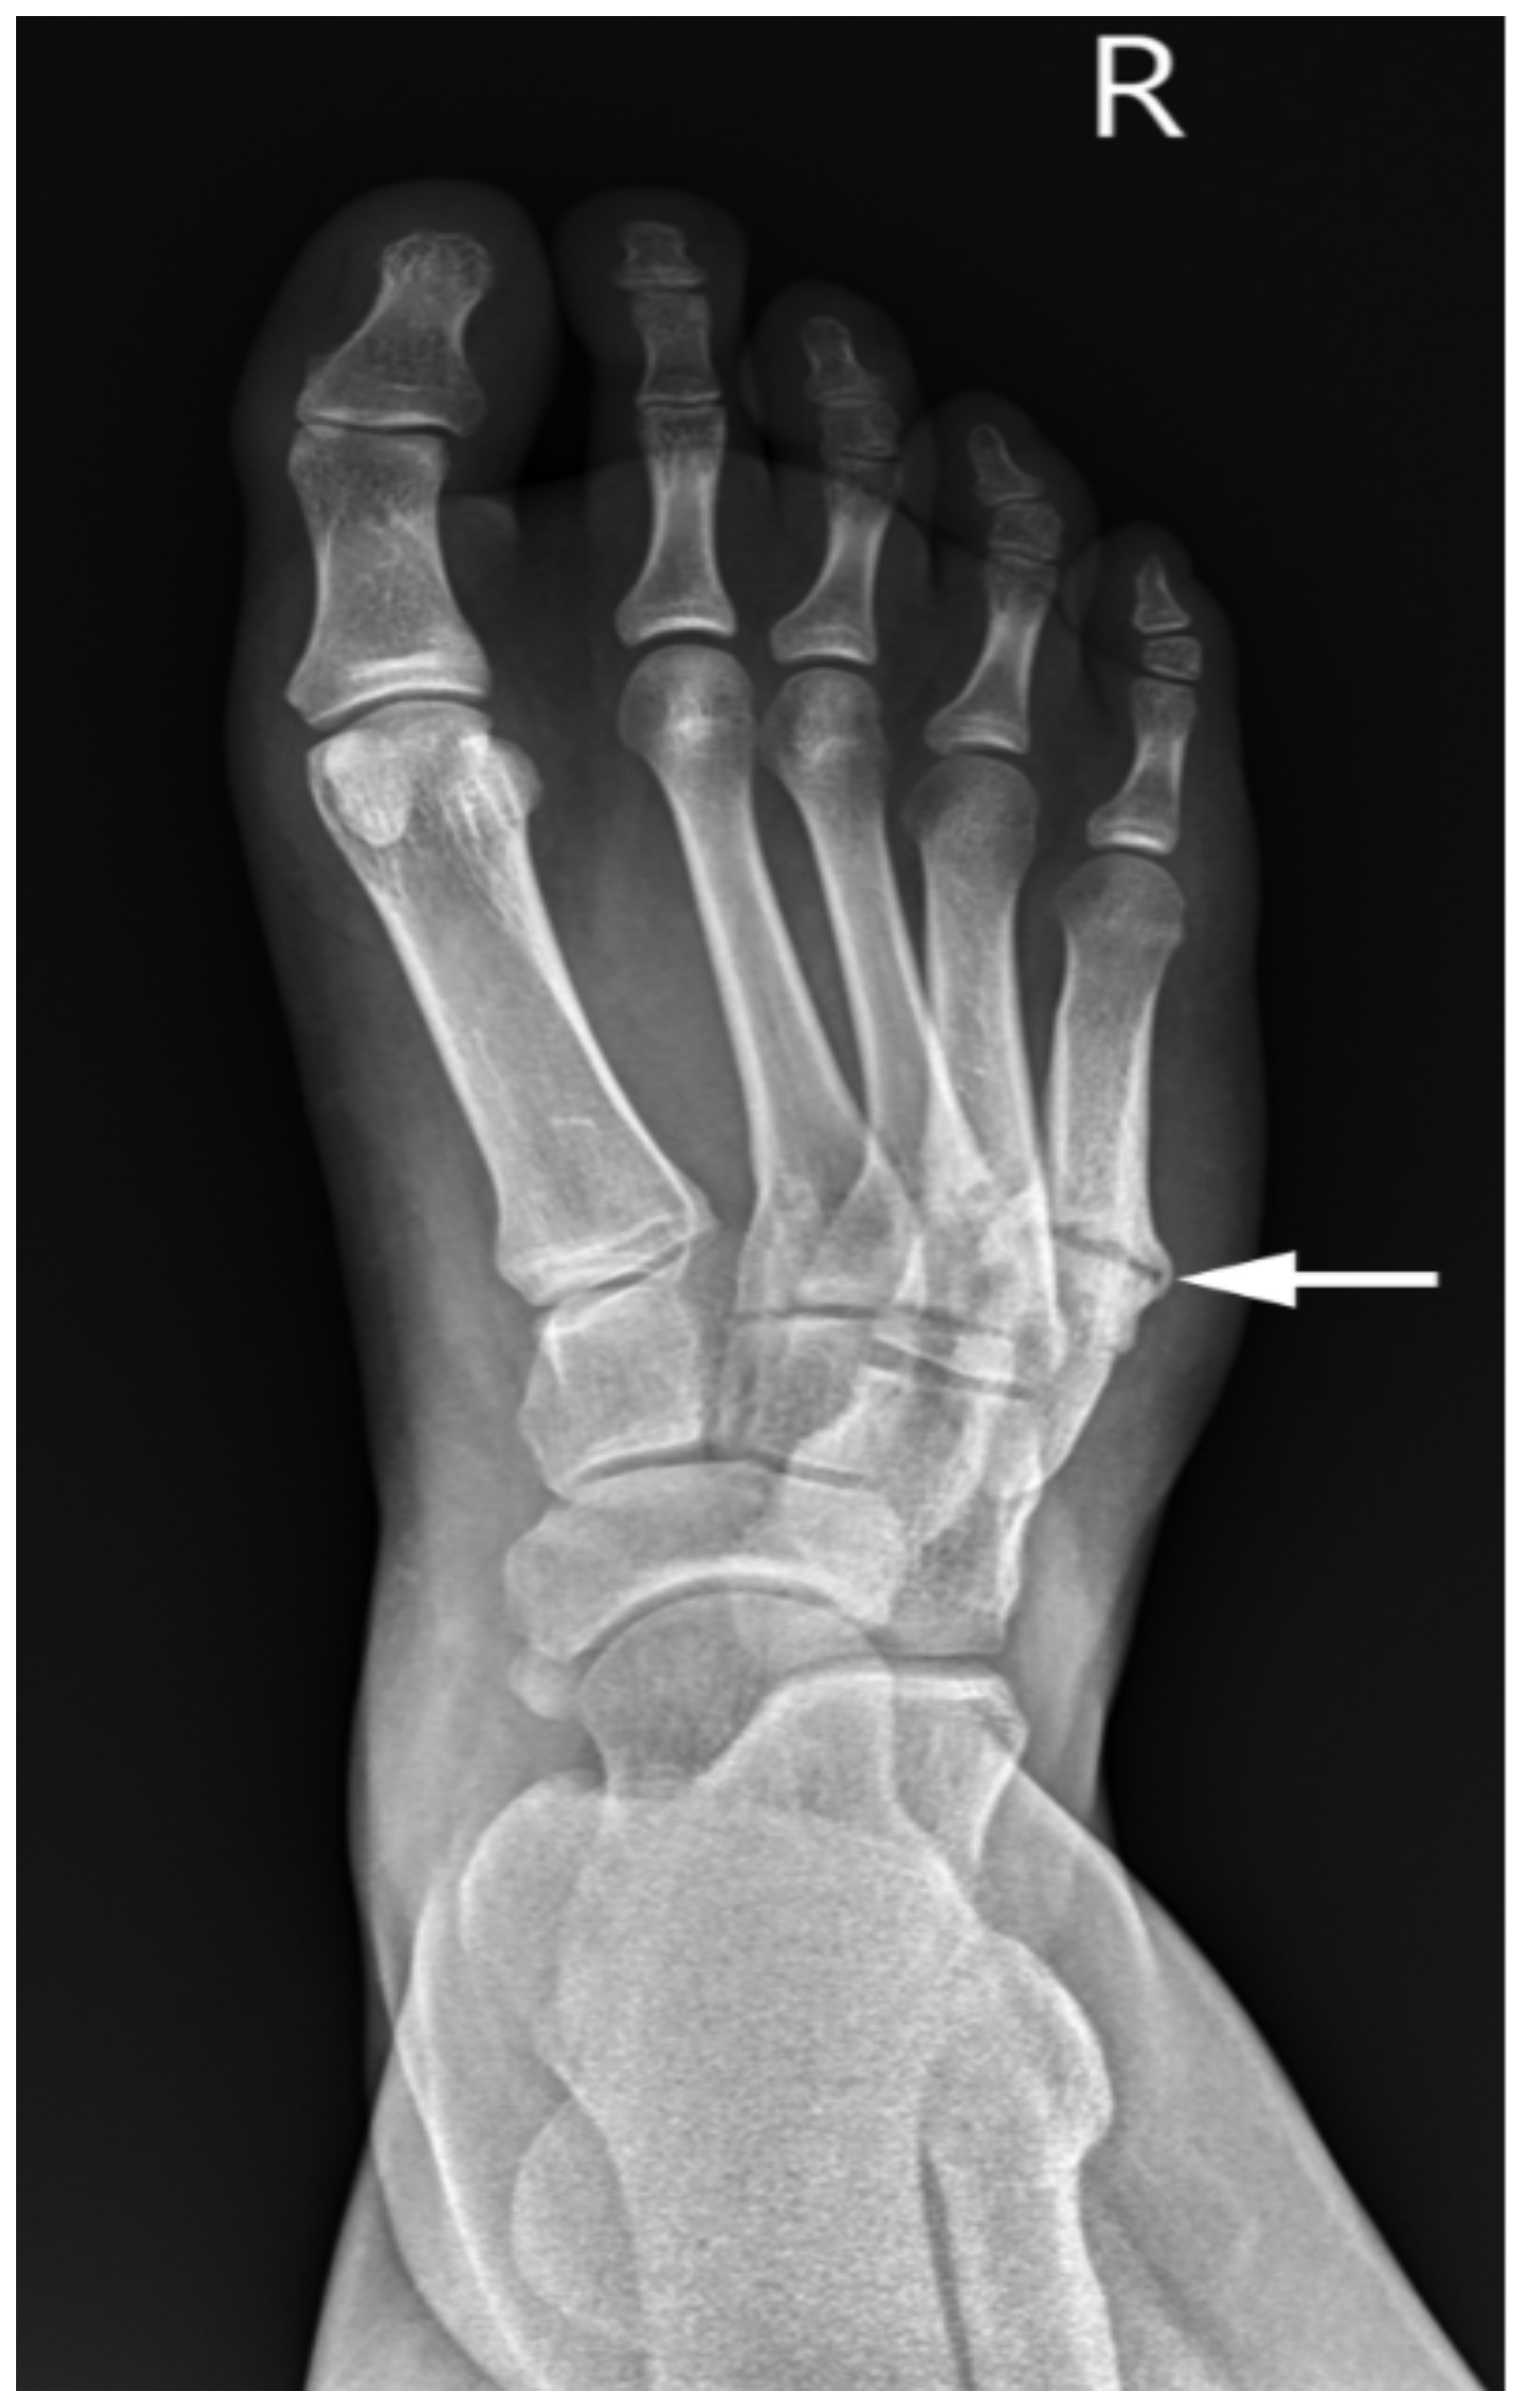

| Foot | Flexible varus or valgus postures. | Partially fixed/flexible varus with muscle imbalance and/or contracture. | Fixed/stiff equino-varus, equinocavovarus. Pes valgus with LAD. Confirmed on radiographs and pedobarography. | Skin callosities and skin breakdown. Stress fractures, metatarsals. Deformed tarsal bones. Arthrosis. |